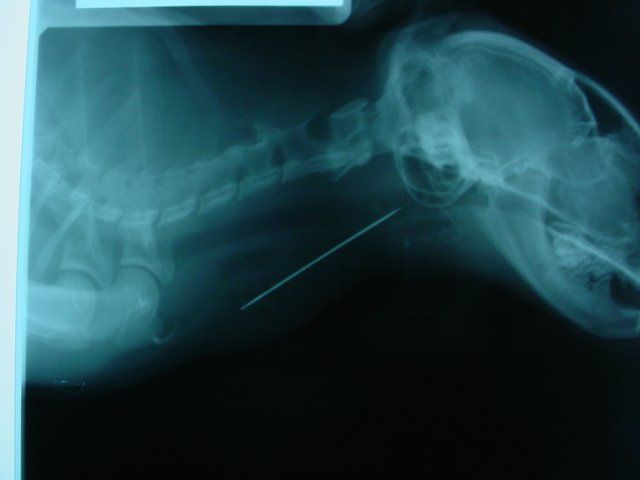

X-rays were taken, and the problem was quickly revealed.

With endoscopy (picture not available), the oral cavity and esophagus were examined for the needle and associated damage. The point of the needle and thread could be seen around the opening to the airway. The thread trailed down into the esophagus.